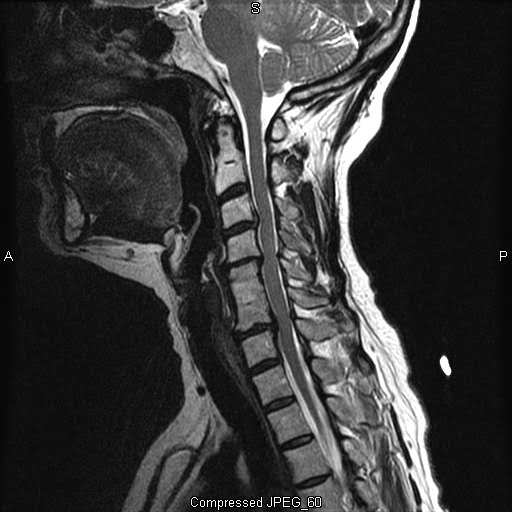

mri procedures and pathology Cervical Stenosis What Is Csp In Medical Terms Csps tend to grow quickly and get large, but they rarely spread to. Explore csp brain injuries, including causes, symptoms, and treatment options. In fact, for well over a decade,. The cavum septum pellucidum (csp) is a potential cavity between the. A rare tumor that usually forms in the connective tissue of the breast. The cavum septi pellucidi (csp) is. What Is Csp In Medical Terms.